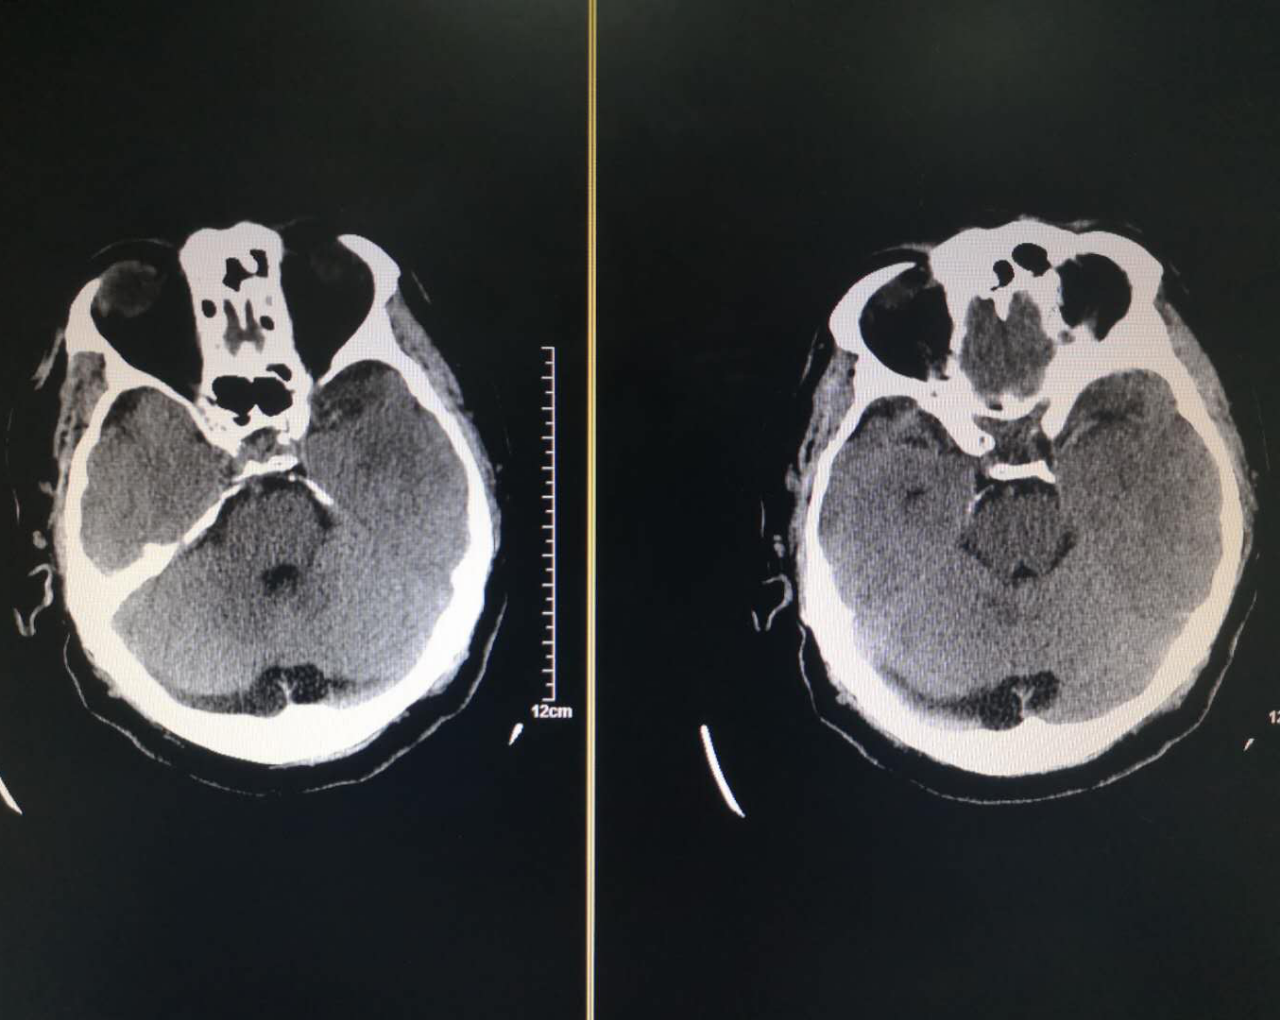

术前头颅CT示

1. 脑内散在腔隙性脑梗死;2. 左侧大脑中动脉近段管腔密度略增高。

术后复查CT未见出血

该患者术前头部CT未见明显出血且发变时间均在手术范围之内,符合急诊取栓手术指征。术中造影提示患者左侧颈内动脉起始部闭塞合并狭窄、左侧大脑中动脉闭塞,急性颈内动脉起始部闭塞合并狭窄是急性缺血性脑血管病中较为严重的一种类型,脑梗死范围常常累及整个大脑中动脉及大脑前动脉供血区域,静脉溶栓血管再通率低,仅为10%左右,急性颈内动脉闭塞预后极差,虽然目前多项研究表明支架取栓或直接抽吸取栓能够改善其预后,但仍面临挑战。在颈内动脉取栓的过程中,由于其特殊的分叉结构,血栓可能向大脑前动脉或者大脑中动脉发生移位或逃逸,也有可能向对侧逃逸,这造成了此处取栓的困难。本例患者在行颈内动脉支架取栓+抽吸后,复查造影提示颈内动脉起始部重度狭窄、左侧大脑中动脉闭塞,考虑串联性病变,再次行支架取栓+抽吸术开通大脑中动脉保证大脑血供,在左侧颈内动脉起始部放置一枚支架,复查造影支架贴壁良好颅内段血供良好。患者术后复查头部CT提示出血,给予对症支持治疗后好转,后期在康复科行康复治疗后出院。